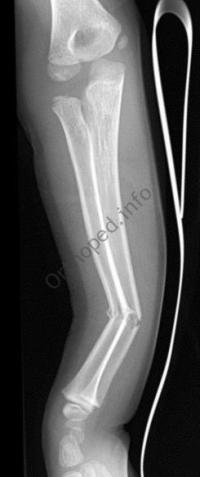

Fracture de l’avant-bras 31 mars 202519 mars 2024 par Damien Traitement Traitement orthopédique Embrochage centro-médullaire